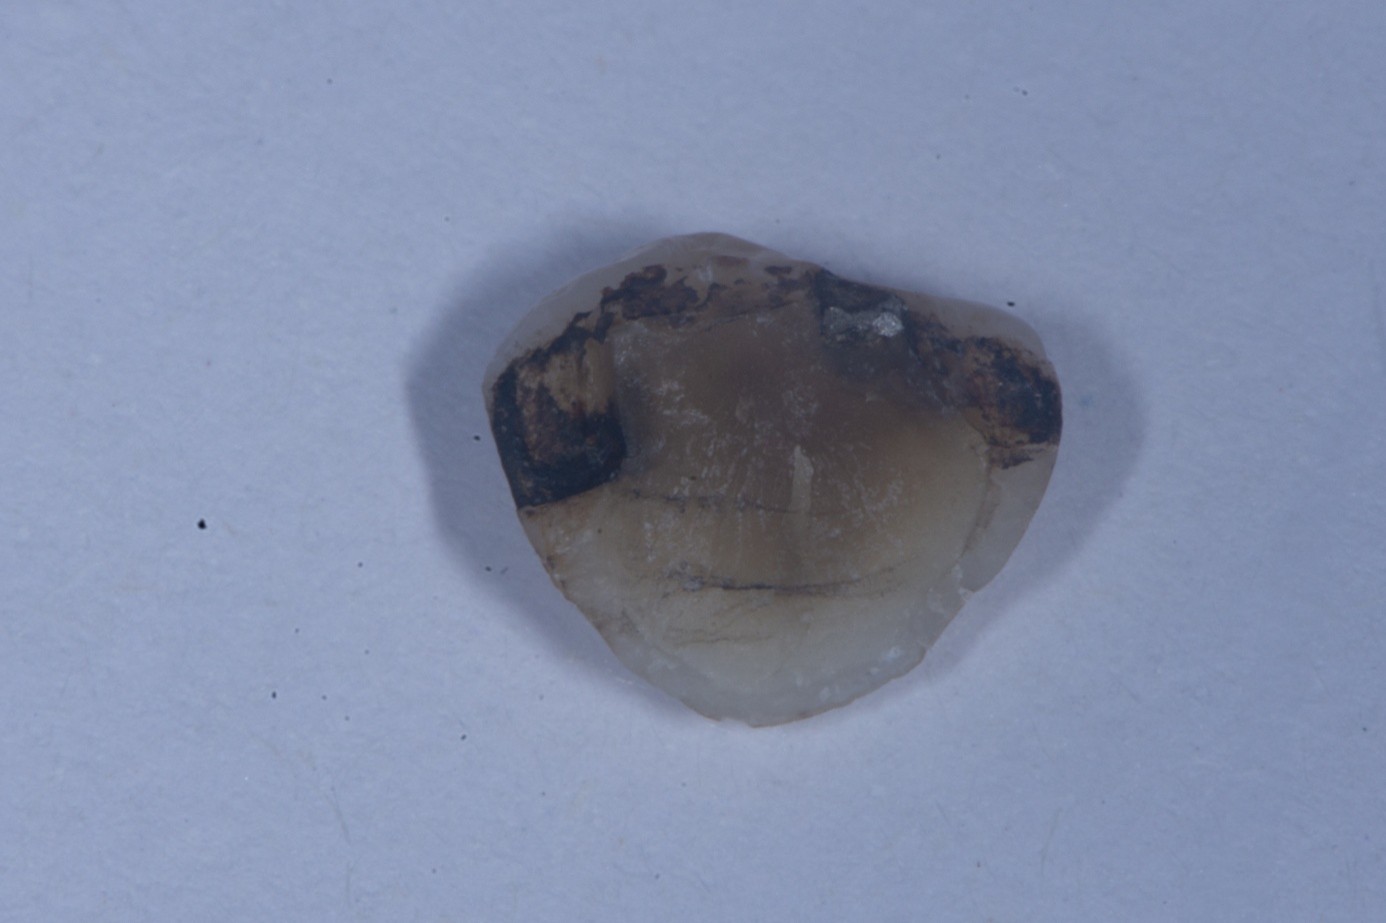

A patient presented on an urgent basis with a fractured buccal cusp of the mandibular second premolar (Figure 32). The tooth had a large MOD amalgam restoration, and the patient fortunately brought the fractured cusp fragment with them. Cuspal fractures of this type are common in teeth restored with amalgam or in teeth with thin, unsupported cusps under bonded restorations. Over time, occlusal forces flex the cusps, leading to crack initiation along the stress plane until catastrophic fracture occurs.

After verifying the fit of the fractured cusp, three-tooth rubber dam isolation was achieved (first premolar to first molar). Dentin adjacent to the fracture line was protected with liquid dam to prevent contamination during amalgam surface preparation (Figure 33). The existing amalgam restoration and fractured surfaces were air-abraded with 27-μm aluminum oxide particles, which effectively cleansed the surface and created micromechanical retention. Care was taken to avoid excessive abrasion of exposed dentin to prevent unnecessary loss of tissue.

(35.) Inner surface of the fractured cusp after sandblasting and enamel etching, showing amalgam staining and small cracks, now prepared for adhesive reattachment.

Figure 35

(36.) Inner surface of the fractured cusp after sandblasting and enamel etching, showing amalgam staining and small cracks, now prepared for adhesive reattachment.

Figure 36